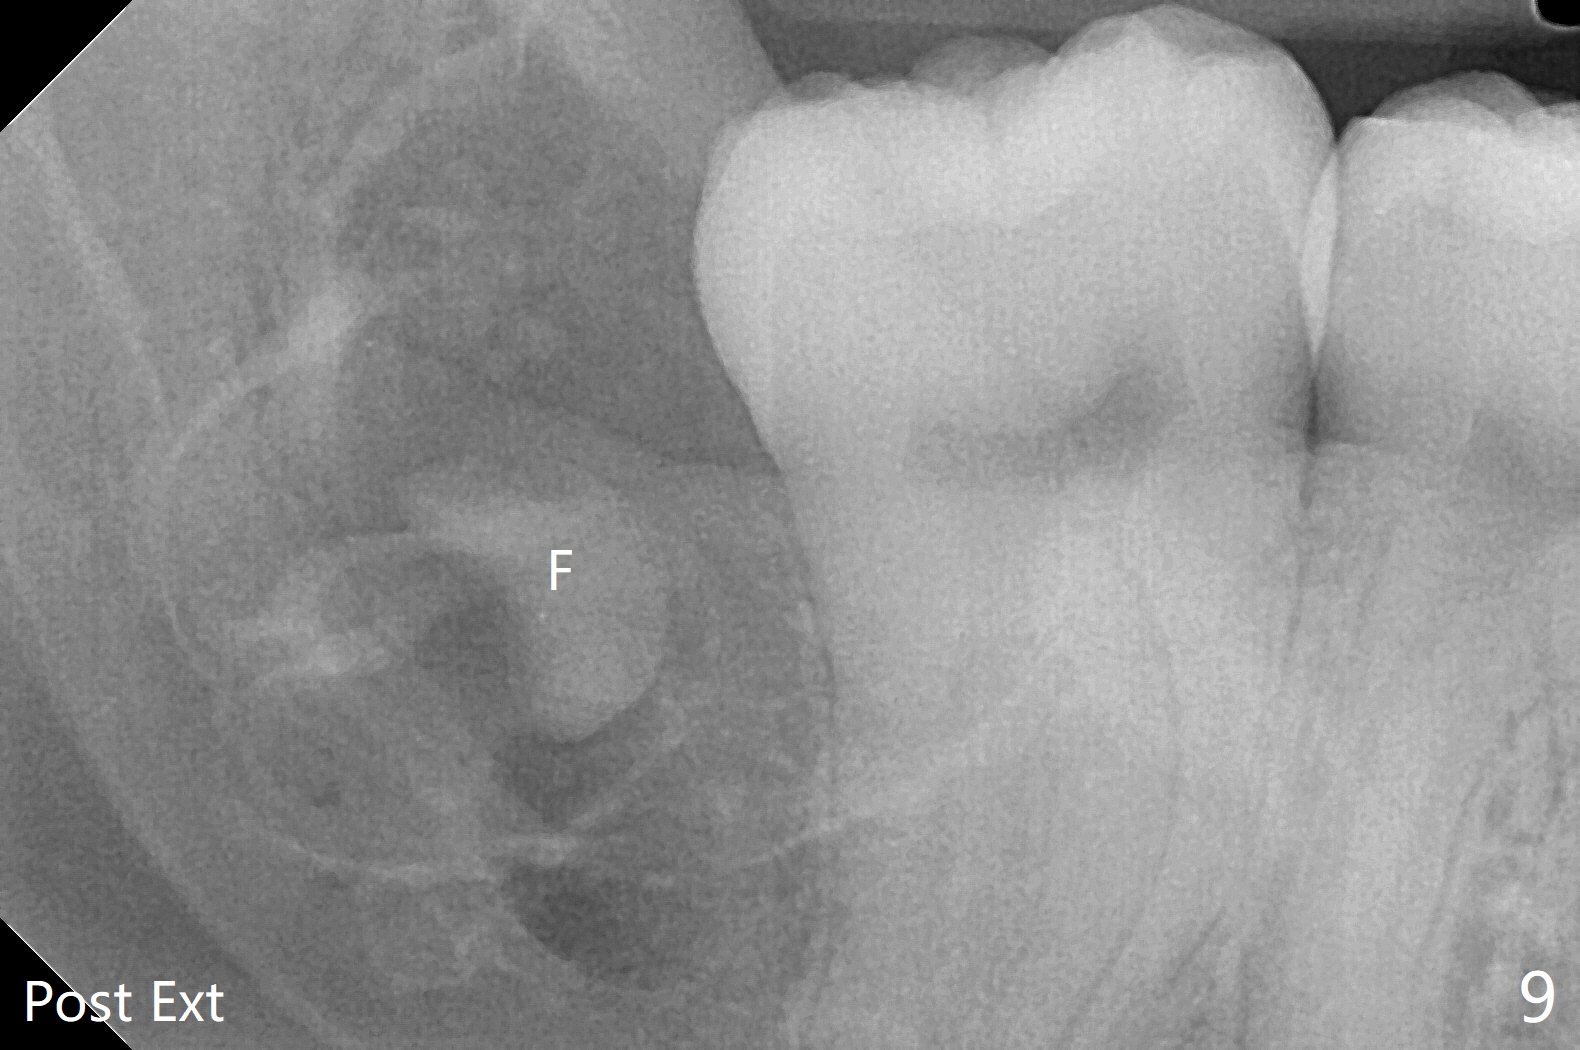

使用胶原塞目的是预防干槽症,以前病例显示它促进骨化中心形成。骨水泥是一种医用性石膏(Biphasic Calcium Sulphate 硫酸钙 ),容易被身体吸收,3个月转换成自体骨。她哥哥(19岁)病例显示骨水泥与Osteogen Plug同样五个月会形成骨质。以后年轻人(25岁以下)智齿拔除不必植骨或者放置骨水泥。左下,右下智齿的确位于第二磨牙颊侧,事先附加切口近中,缝合后伤口不易裂开,骨粉丢失。拔除后即刻拍摄根尖片(图九,十),目的建立原有解剖,与愈合后比较,意外发现断裂牙片(F),后来取出。